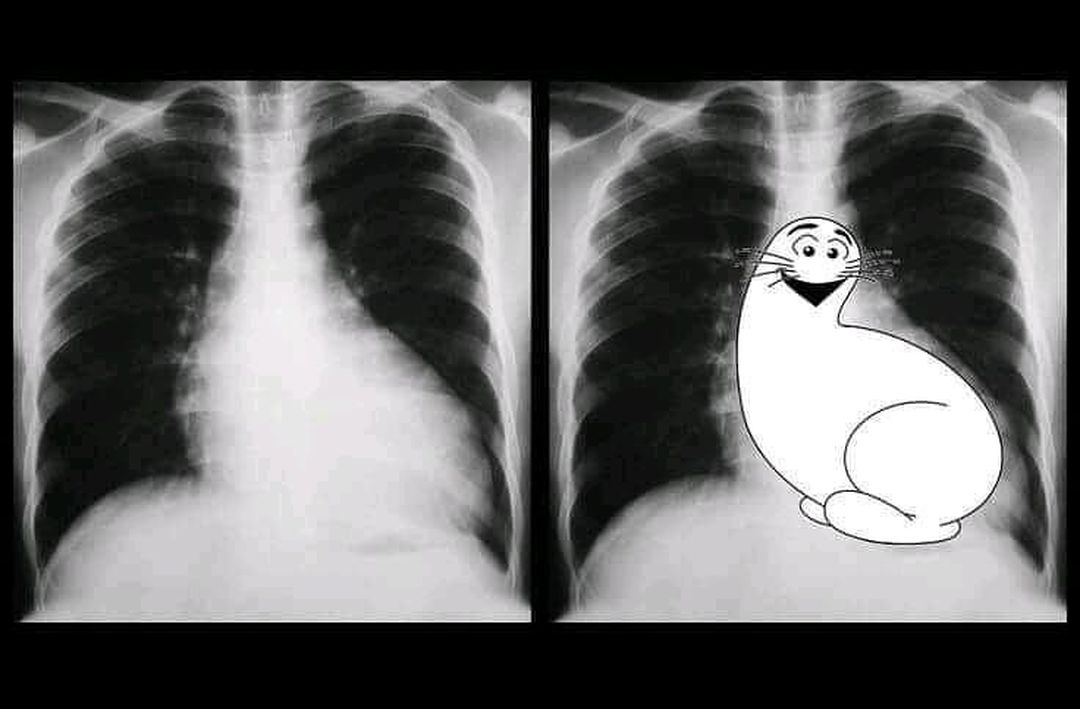

Shmoo sign refers to the appearance of a prominent, rounded left ventricle and dilated aorta on a plain AP chest radiograph giving the appearance of Shmoo, a fictional cartoon character in the comic strip Li'l Abner, which first appeared in 1948. This sign is indicative of left ventricular enlargement.